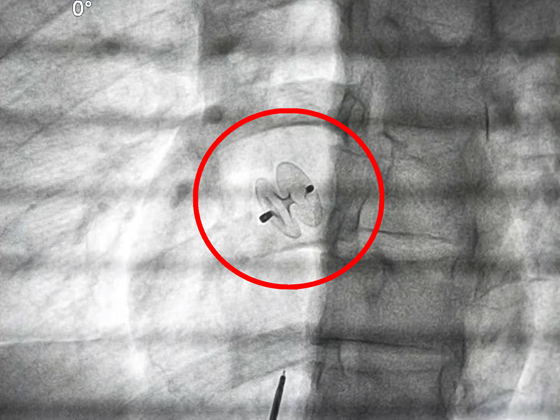

术中

为患者成功植入封堵器

完善术前准备后,心血管内科介入团队在彭道地副教授和范爱德主任医师的带领下,顺利植入封堵器,手术过程顺利,没有出现并发症。